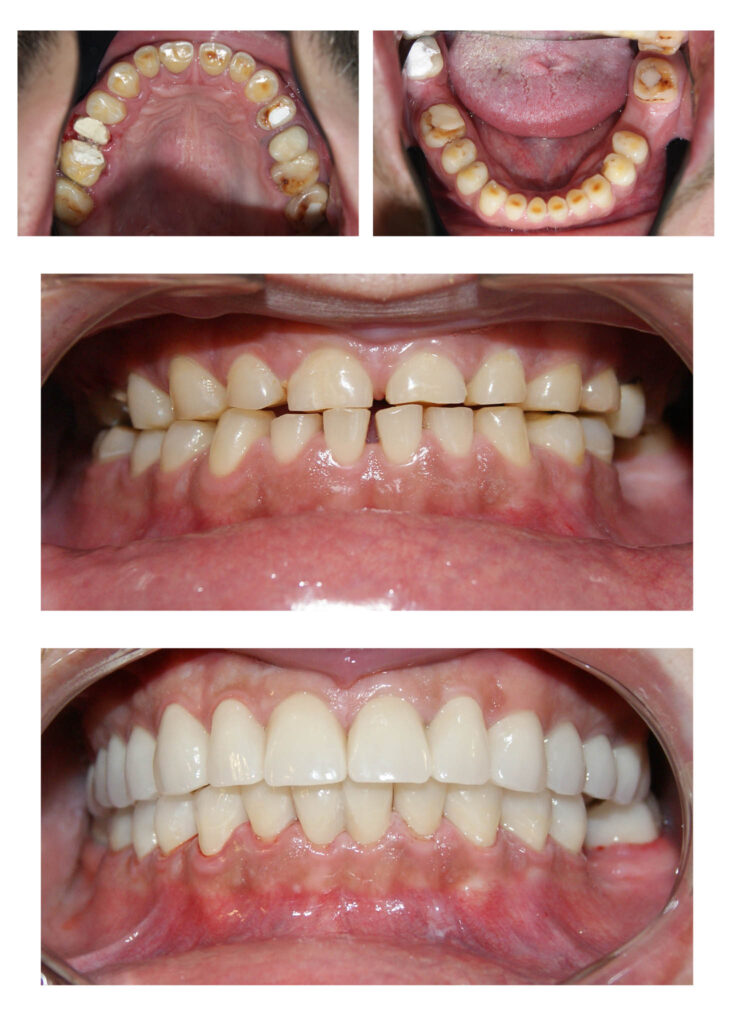

Reabilitare complexă și completă a dinților cu un accent grav de uzură, a dimensiunii verticale de ocluzie și a zâmbetului = restabilirea tuturor funcțiilor naturale